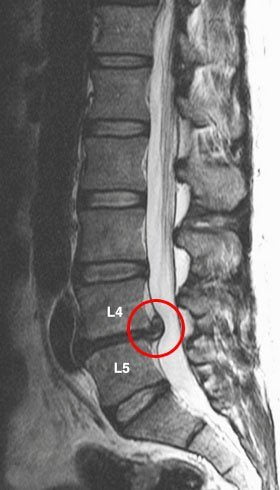

Тянущая, постоянная ноющая боль в пояснице может быть спровоцирована воспалением органов малого таза. Но в подавляющем большинстве случаев она указывает на деструктивно-дегенеративные изменения в межпозвонковых дисках и позвонках. Острая боль в поясничном отделе характерна для воспаления нервного корешка или его сдавления, травмирования сформировавшейся межпозвоночной грыжей.

Ведущий симптом всех патологий позвоночника — боль в спине. Ее появление справа типично для одностороннего ущемления нервного корешка. Это часто происходит при остеохондрозе шейно-грудного, грудного, поясничного, пояснично-крестцового отделов позвоночника. Особенно часто боли возникают при его уже развившихся осложнениях: протрузии, межпозвоночной грыже, дискогенной миелопатии, корешковом синдроме.

Повреждение дисков, позвонков, а особенно сдавление спинномозговых корешков редко проявляются четко локализованными болями. Они распространяются на рядом расположенные участки тела, иррадиируют в руки, ноги, бока.

Остеохондроз межпозвоночных дисков поясницы – наиболее частая причина. Короткие болевые приступы в нижней части спины могут начаться после сильных движений, кашля, чиха и смеха. В эти моменты может проявиться прострел спины (как его еще называют, люмбаго). В таком состоянии человек на некоторое время теряет возможность двигаться от боли. Приступы в этой ситуации часто начинают иррадировать в бедра и ягодицы с разной силой.

Спондилез всегда вызывает резкие боли в пояснице справа, если пациент наклоняется, лежит на левой стороне тела, долго не меняет позу, в которой расположился. Часто боли перерождаются во временную хромоту из-за потери чувствительности нижних конечностей. Этот симптом может уйти так же неожиданно, как пришел.

Главным виновником боли в спине является остеохондроз. Локализация болезненных ощущений будет зависеть от того, какой участок позвоночника патологически изменен. Чаще всего страдает поясничный отдел позвоночника. При этом возникает постоянная ноющая боль внизу справа или слева. При поражении грудного отдела, болезненные ощущения могут локализироваться выше поясницы или под лопаткой.

При развитии осложнений остеохондроза (защемление нервов, их воспаление — радикулит) боль приобретает другой характер.

Развивается проецируемый болевой синдром – болезненные ощущения иррадиируют по ходу вовлеченных нервных окончаний (в руку, в ногу). Такая боль может иметь постоянный характер (люмбалгия, торакалгия) или в виде прострела (люмбого, торакаго).